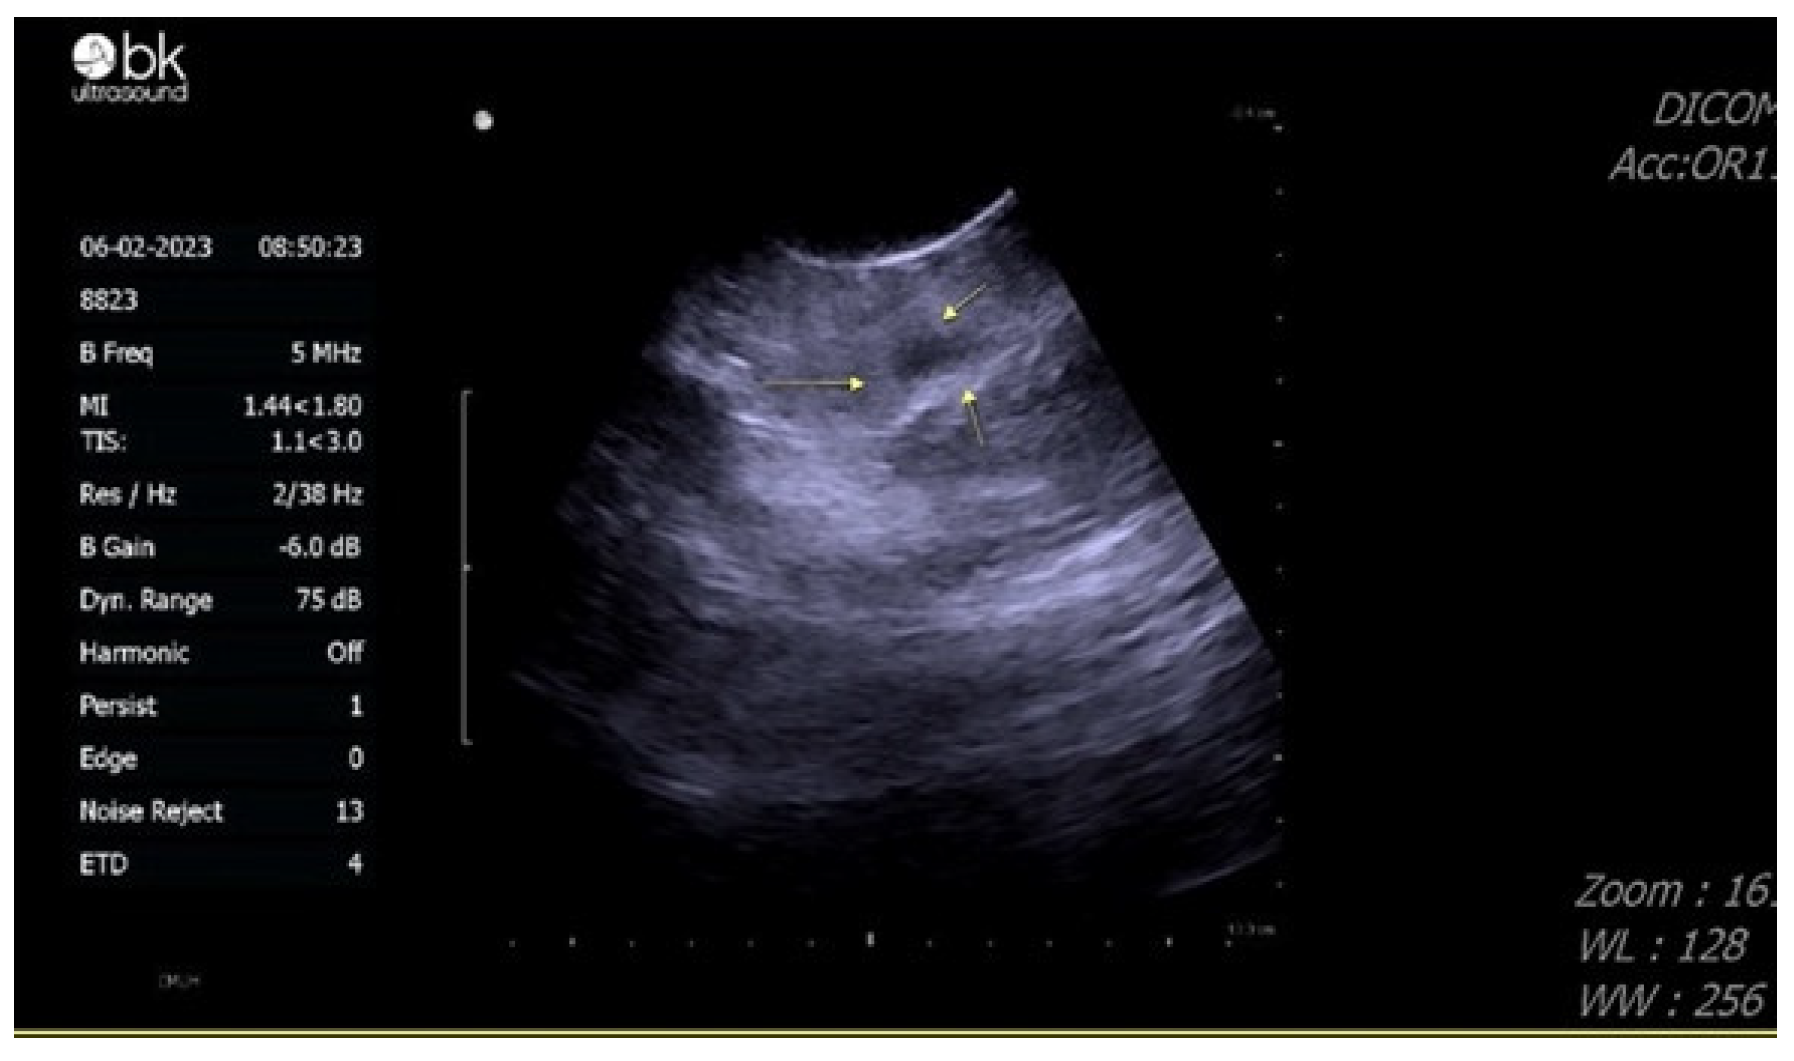

2. Case Presentation